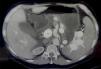

Por medio de una tomografía computarizada abdominal y pélvica con contraste se observó la arterialización de la vasculatura portal con parénquima hepático normal, ascitis normal y esplenomegalia, descartando otras causas de la hipertensión portal y la ascitis (fig. 1). Con imágenes adicionales se observó comunicación entre la arteria y la vena esplénica. La angiografía confirmó FAEE, la cual fue tratada con embolización con espiral vía arteria femoral con vaina 6F. La arteria esplénica fue canulada con un catéter CobraC25F. La angiografía por sustracción digital (DSA) reveló una dilatación por aneurisma de la vena esplénica, sin opacificación del parénquima esplénico (fig. 2). La fístula se embolizó con éxito utilizando espirales colocadas con microcatéter (fig. 3). Posterior al procedimiento, la ascitis de la paciente y las várices esofágicas mejoraron y un año después no requirió de betabloqueadores o diuréticos, ni presentó signos de hipertensión portal clínicamente significativa.